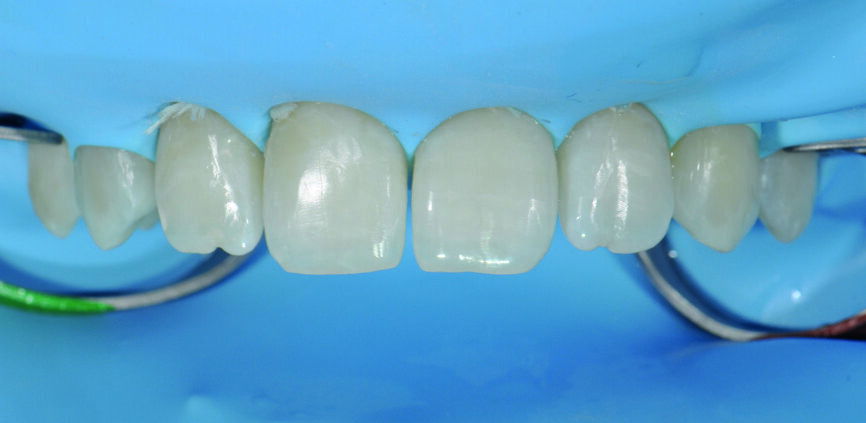

Fig. 5 : a) Après la mise en place de la digue en caoutchouc.

Fig 5b) : Les surfaces dentaires ont été légèrement sablées pour obtenir une performance adhésive optimale.

Fig 5 c) : La sélection des matrices et une mise en place adéquate sont importantes pour créer un profil d’émergence naturel.